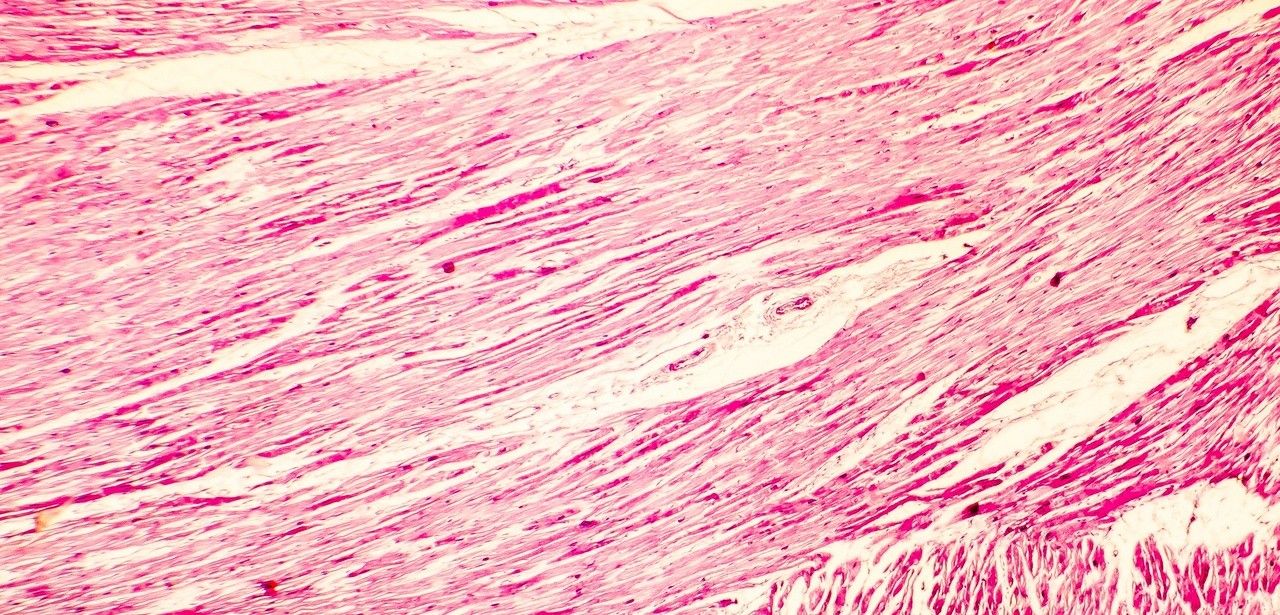

Bei Herzinsuffizienz handelt es sich um eine chronische Erkrankung, bei der das Herz nicht mehr in der Lage ist, das Blut effektiv genug durch den Körper zu pumpen. Bei kongestiver Herzinsuffizienz kommt es zu einer Ansammlung von Blut im Gewebe, was zu Symptomen wie Schwellungen in den Beinen und Knöcheln führen kann. Weltweit sind etwa 26 Millionen Menschen von dieser Art der Herzinsuffizienz betroffen.